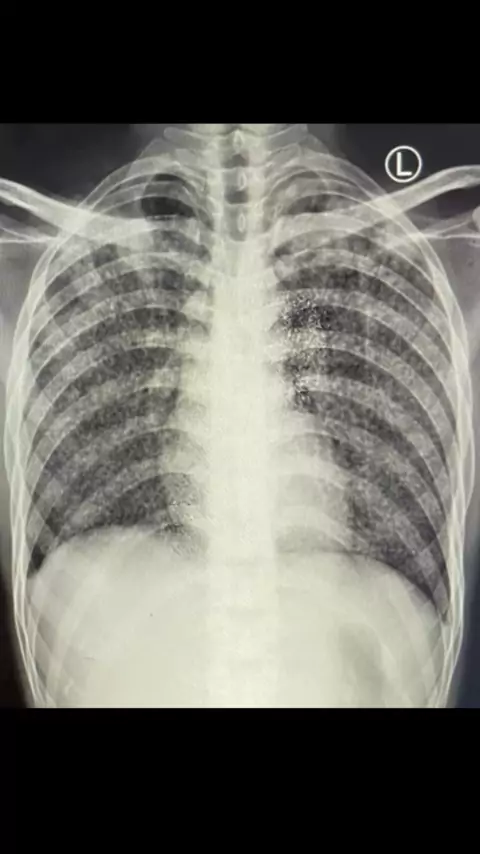

Foto Toraks atau rontgen paru Penyakit TB Paru#tuberculosis#tbcparu#tbparu#chestxray#xray#chest#radiologi#radiology#dokterparu#spesialisparu#viral#viralvideo#viral#edukasi゚viral##